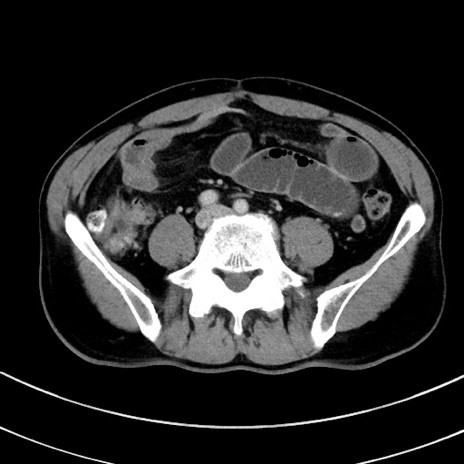

症例8(横断像)

【症例】 60歳代男性

【主訴】 黒色吐物

【現病歴】 4日前から嘔気自覚、2日前の朝食後にも嘔気あり、自分で手で嘔吐反射起こし嘔吐したところ血が混ざっていたため受診。

【既往歴】 5年前汎発性腹膜炎を伴う急性虫垂炎で手術、高血圧、前立腺肥大症、高脂血症

【身体所見】 腹部正中に手術癩痕あり 腹部平坦・軟圧痛なし膨満感あり

【データ】WBC 8400、CRP 4.54